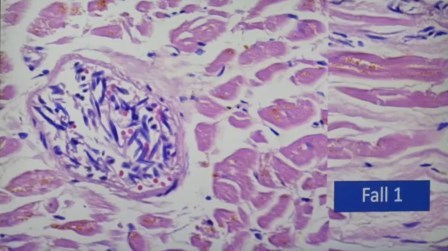

He aquí lo mostrado. Primero, en corazón:

Destrucción de la fibra muscular y el edema

Lo mismo, los puntitos negros que son los linfocitos

Con aumento se ve la vasodilatación, linfocitos, fibroblastos

Aquí es más notable la destrucción de la fibra muscular

Aquí el edema muy visible

Multfocales

Los puntos negros son infiltración de linfocitos en la parte decisiva

Foco de infección en otro sitio y no había una oclusión coronal, quiere decir que no se debe a los vasos sanguíneos, sino la inflamación que se manifiesta de manera múltiple

Aquí se ve el fenómeno que se llama la «pila de dinero»

Ampliación, linfocitos y granulocitos. Los linfocitos no deben estar allí, pero están omnipresentes, se trata de una epicarditis

Epicardio con infiltración de linfocitos

Estas miocarditis vistas no son por virus sino por sustancias de la vacuna